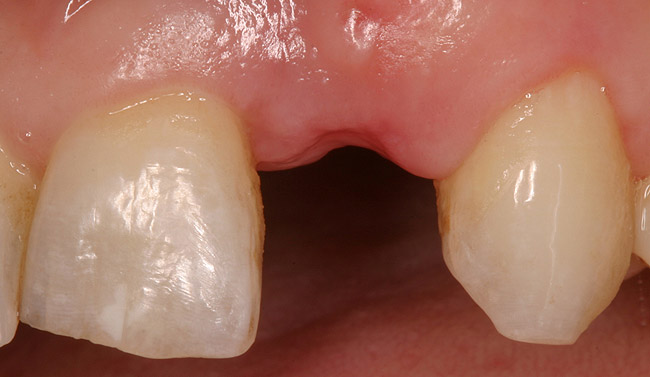

Figure 6a  Upper right central incisor, history of trauma, existing RCT and restoration unsatisfactory.

Figure 6a

Figure 6b  Upper right central incisor, history of trauma, existing RCT and restoration unsatisfactory.

Figure 6b

Figure 6c  Upper right central incisor, history of trauma, existing RCT and restoration unsatisfactory.

Figure 6c

Figure 6d Completed treatment: revised RCT, zirconium post/pressed ceramic core cemented with Panavia 21¬Æ Resin Cement (Kuraray Dental). All-ceramic full-coverage crown cemented with Kerr NX3 Nexus¬Æ Third Generation Dual Cure Resin cement. Implant therapy not indicated.

Figure 6d

Figure 6e  Completed treatment: revised RCT, zirconium post/pressed ceramic core cemented with Panavia 21¬Æ Resin Cement (Kuraray Dental). All-ceramic full-coverage crown cemented with Kerr NX3 Nexus¬Æ Third Generation Dual Cure Resin cement. Implant therapy not indicated.

Figure 6e

Figure 6f  Completed treatment: revised RCT, zirconium post/pressed ceramic core cemented with Panavia 21¬Æ Resin Cement (Kuraray Dental). All-ceramic full-coverage crown cemented with Kerr NX3 Nexus¬Æ Third Generation Dual Cure Resin cement. Implant therapy not indicated.

Figure 6f